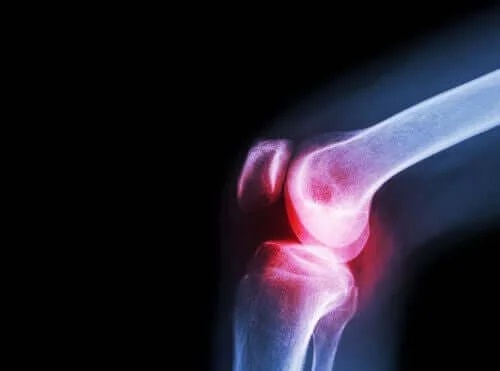

Celălalt simptom comun al lupusului eritematos sistemic este durerea articulară. Aceasta este produsă de artrita declanșată de reacția autoimună. Evoluția acestei artrite presupune atacuri acute, cu perioade fără durere și perioade cu dureri mari.